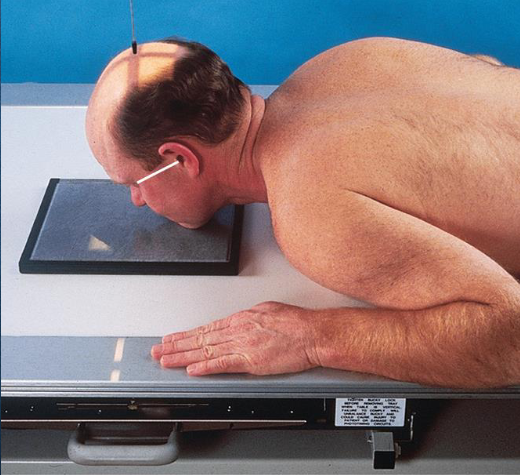

Lateral orbits

patient position:

upright or recumbent anterior oblique position

part position:

outer canthus of affected eye adjacent and centered to IR

adjust patient’s head to place MSP parallel with IR

IPL perpendicular to IR

flex neck to place IOML perpendicular to front edge of IR

respiration suspended

CR:

perpendicular through outer canthus

Lateral orbits image criteria

entire orbit(s)

no rotation

superimposed orbital roofs

close beam restruction centered to orbital region

PA axial (exaggerated Caldwell) orbits

patient position:

upright or recumbent

part position:

rest forehead and nose on IR

IR centered ¾ inches distal to nasion

adjust head to place MSP and OML perpendicular to IR

respiration suspended

CR:

30 degrees caudad, through center of orbits

non-grid technique recommended to reduce magnification and eliminate possible artificats